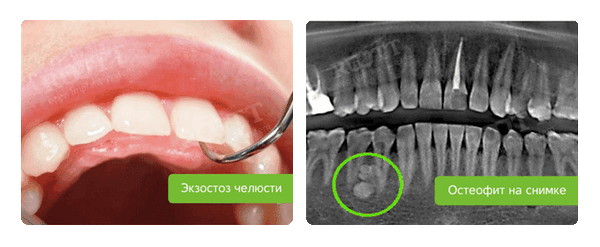

Также удаляют наросты кости - остеофиты и экзостозы. Слой покрывающей их слизистой очень тонкий, протез легко поранит ее и будет натирать, вызывая боль и неудобство. Поэтому их убирают, выравнивая край десны.

Как выглядит экзостоз

- Удаление имеющихся экзостозов и остеофитов, создающих помехи для установки протеза;

- Устранение корней моляров (в случае кисты, периодонтита, гранулемы), экзостозов (шиповидных выростов костной ткани).